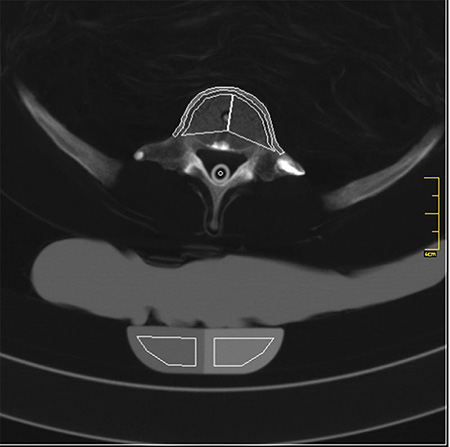

德國(guó)Erler Zimmer 7200天然骨骼全身模體,EZ 7200全身模體包含一個(gè)真實(shí)的人體骨骼,可以像患者一樣拍攝真正的X射線圖像。使用真實(shí)的骨架可以提供最小的導(dǎo)向結(jié)構(gòu),這對(duì)于塑料骨架來說是不可能的。

在組裝這個(gè)模體時(shí),我們特別注意關(guān)節(jié)空間的正確尺寸。所有關(guān)節(jié)都可移動(dòng)地安裝,允許定位在所有正常的X射線位置。手臂可以向上移動(dòng),這使得模體適合用于CT下的各種骨質(zhì)檢查。

軟組織和器官:聚氨酯基樹脂(SZ-50)  骨骼:真人骨骼

2、全身X線CT教學(xué)模體、真人骨骼,人工材料逼真的心臟、肺、吼和腎臟等;

7、滿足任意部分進(jìn)行X線/CT掃描,成像效果與真實(shí)人體一致,影像片中能正常分辨出骨齡。

The phantom contains a real human skeleton, which allows taking real X-ray images like in a patient. Using a real skeleton provides even smallest guiding structures which is impossible with a plastic skeleton.

During assembly of this phantom we pay special attention to the correct size of joint spaces. All joints are moveably mounted allow positioning in all normal x-ray positions. The arms can be moved upwards which makes the phantom suitable for use in all kinds of osseous examinations under CT.